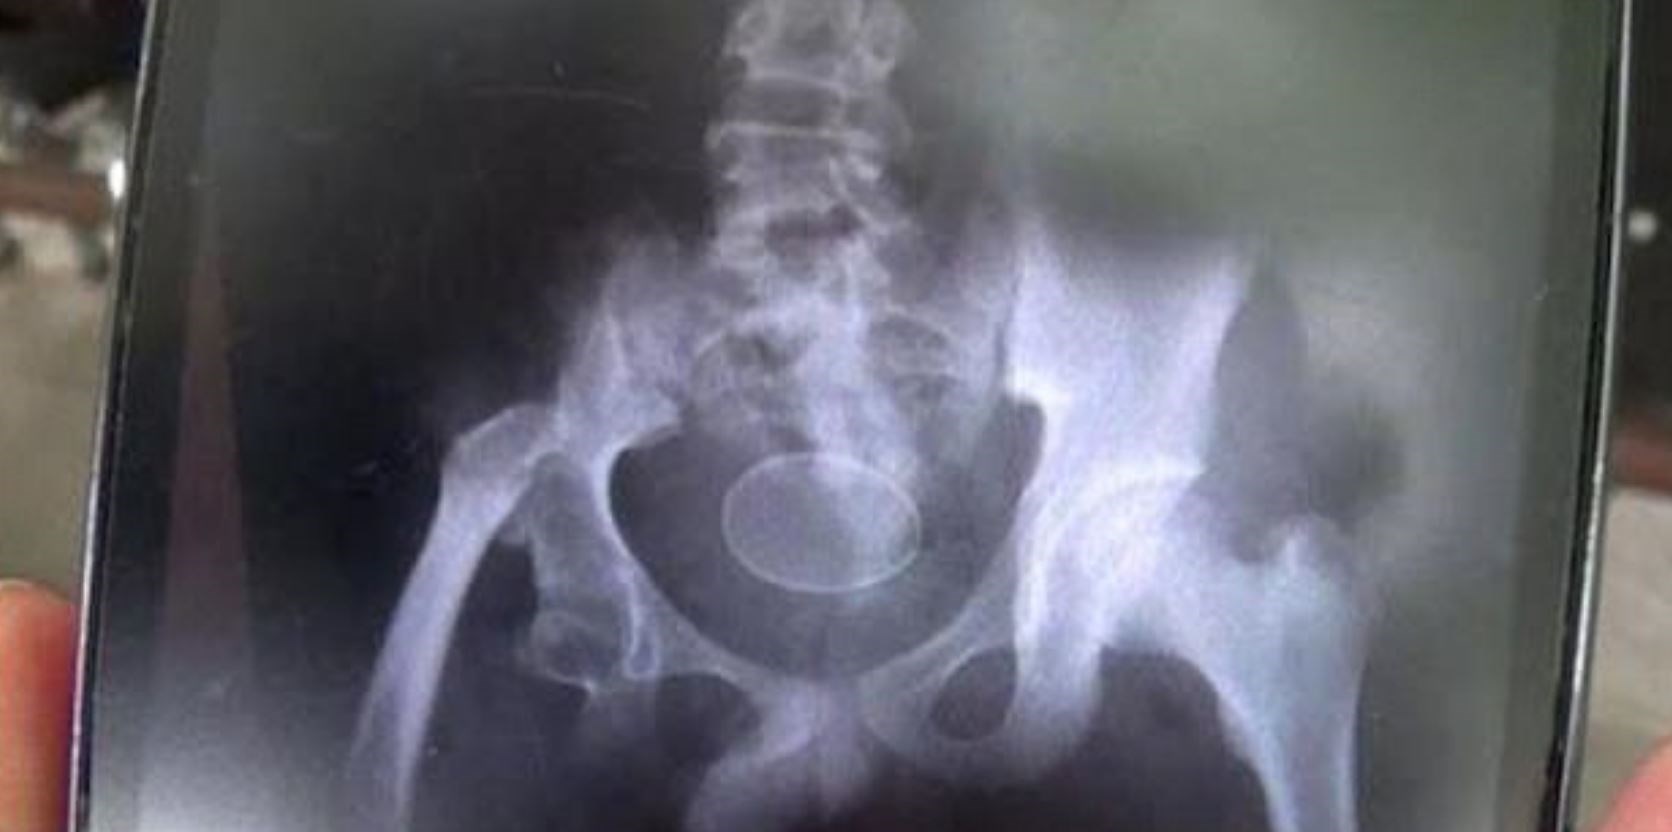

Τον ρώτησαν αν τα κατάπιε και το αρνήθηκε. Οι γιατροί τον πίστεψαν, καθώς τα αυγά ήταν ολόκληρα στην κοιλιά του. Τελικά, οι γιατροί αφαίρεσαν με επέμβαση τα δύο αυγά από την κοιλιά του 14χρονου, ωστόσο, ο πατέρας του τους ενημέρωσε πως όταν το παιδί ήταν 12 ετών είχε μεταφερθεί με έντονους πόνους και πρήξιμο στο νοσοκομείο και οι γιατροί διαπίστωσαν ότι υπήρχαν 18 αυγά μέσα στην κοιλιά του, αλλά και στο έντερο. Σε εκείνη την περίπτωση, τα αυγά αφαιρέθηκαν από το παιδί μέσω του πρωκτού και του χορηγήθηκε ειδική αγωγή.

«Η αρχική μας υποψία ήταν ότι τα αυγά σκοπίμως εισήχθησαν μέσω του πρωκτού στο εσωτερικό του σώματος του παιδιού. Στις εξετάσεις που κάναμε, ωστόσο, δεν διαπιστώσαμε κάτι τέτοιο. Είναι παράδοξο. Τα αυγά κότας δεν είναι δυνατόν να σχηματιστούν μέσα στο ανθρώπινο σώμα και στο πεπτικό σύστημα», δήλωσε ένας από τους θεράποντες ιατρούς του παιδιού.